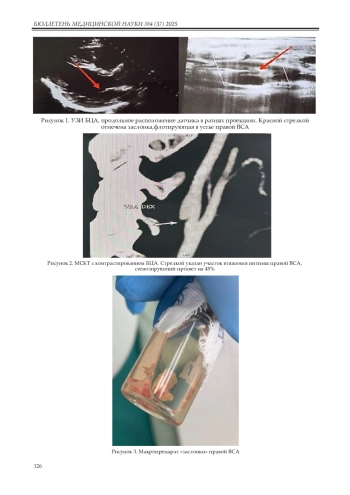

Каротидная мембрана является важной, но часто недиагностируемой патологией у пациентов с криптогенными инсультами, особенно у пациентов молодого и среднего возраста. В данной публикации описывается хирургическое лечение редкой аномалии внутренней сонной артерии (ВСА) у 50-летнего пациента, перенесшего два криптогенных инсульта в течение четырех месяцев. При обследовании общепринятых факторов риска развития ишемического инсульта у пациента не было выявлено, а МСКТ-АГ и гистологическое исследование интраоперационного материала подтвердило диагноз каротидной мембраны. Пациенту была выполнена КЭЭ с аутовенозной пластикой ВСА. Этот клинический случай подчеркивает важность рассмотрения каротидных заслонок в дифференциальной диагностике инсультов у молодых пациентов с повторными однополушарными инсультами без факторов риска и подтверждает необходимость хирургического лечения для профилактики повторных инсультов.